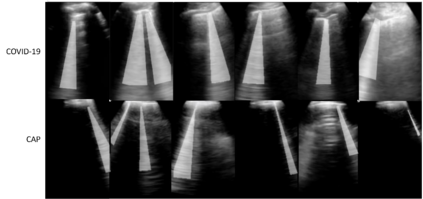

Lung ultrasound imaging has been shown effective in detecting typical patterns for interstitial pneumonia, as a point-of-care tool for both patients with COVID-19 and other community-acquired pneumonia (CAP). In this work, we focus on the hyperechoic B-line segmentation task. Using deep neural networks, we automatically outline the regions that are indicative of pathology-sensitive artifacts and their associated sonographic patterns. With a real-world data-scarce scenario, we investigate approaches to utilize both COVID-19 and CAP lung ultrasound data to train the networks; comparing fine-tuning and unsupervised domain adaptation. Segmenting either type of lung condition at inference may support a range of clinical applications during evolving epidemic stages, but also demonstrates value in resource-constrained clinical scenarios. Adapting real clinical data acquired from COVID-19 patients to those from CAP patients significantly improved Dice scores from 0.60 to 0.87 (p < 0.001) and from 0.43 to 0.71 (p < 0.001), on independent COVID-19 and CAP test cases, respectively. It is of practical value that the improvement was demonstrated with only a small amount of data in both training and adaptation data sets, a common constraint for deploying machine learning models in clinical practice. Interestingly, we also report that the inverse adaptation, from labelled CAP data to unlabeled COVID-19 data, did not demonstrate an improvement when tested on either condition. Furthermore, we offer a possible explanation that correlates the segmentation performance to label consistency and data domain diversity in this point-of-care lung ultrasound application.